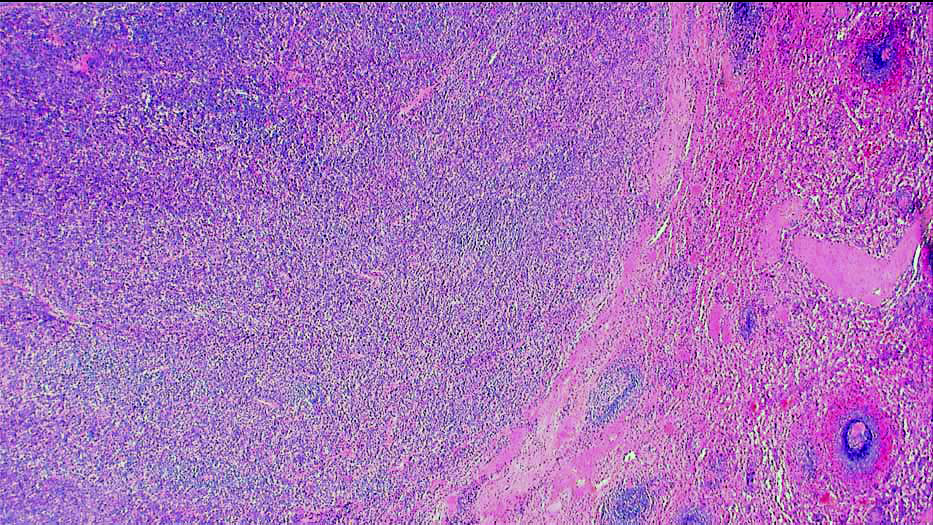

| 肉眼所見 |

弱拡大 |